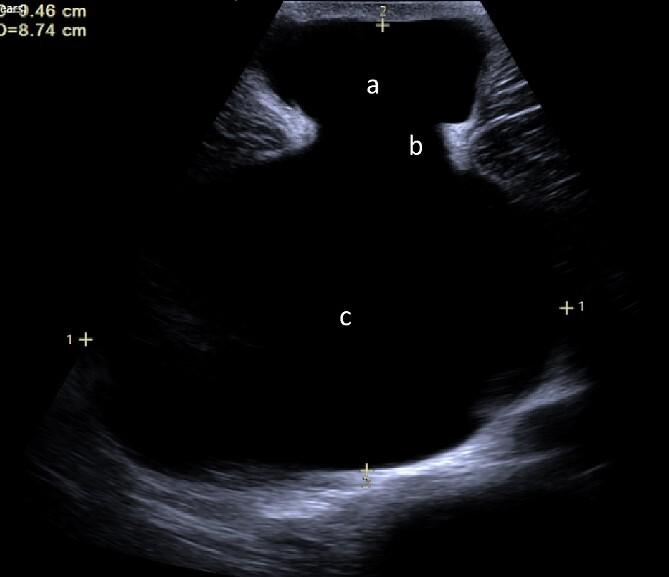

Peritoneal inclusion cysts (PICs) are a rare and benign condition of uncertain pathogenesis. The fluid-filled, mesothelial-lined cysts manifest within the abdominopelvic cavity. This case report details an unusual occurrence of a 97 mm PIC- presenting as an umbilical hernia- in a 26-year-old male patient with no prior surgical history. Following pre-operative cross-sectional imaging, this was managed through open excision without complication. A systematic review of the literature highlighted 30 previous cases [26F, 4M] with a mean age of 34 years (std ±15.4) and a median diameter of 93 mm [IQR, 109 mm]. A total of 53% (n = 16) of cases had a history of previous abdominal surgery. Surgical excision is safe and laparoscopic modality should be considered (<1% recurrence). Accepting the limited evidence base, image guided drainage should be avoided (50% recurrence, n = 2).

腹膜包涵囊肿(PICs)是一种发病机制不明的罕见良性疾病。这种充满液体、由间皮细胞衬里的囊肿出现在腹腔盆腔内。本病例报告详细描述了一名26岁无手术史男性患者出现的一例罕见的97毫米腹膜包涵囊肿,表现为脐疝。术前进行横断面成像检查后,通过开放切除进行处理,未出现并发症。对文献的系统回顾显示,此前有30例病例报道[26例女性,4例男性],平均年龄为34岁(标准差±15.4),中位直径为93毫米[四分位间距,109毫米]。共有53%(n = 16)的病例有腹部手术史。手术切除是安全的,应考虑采用腹腔镜手术方式(复发率<1%)。鉴于证据有限,应避免影像引导下引流(复发率50%,n = 2)。